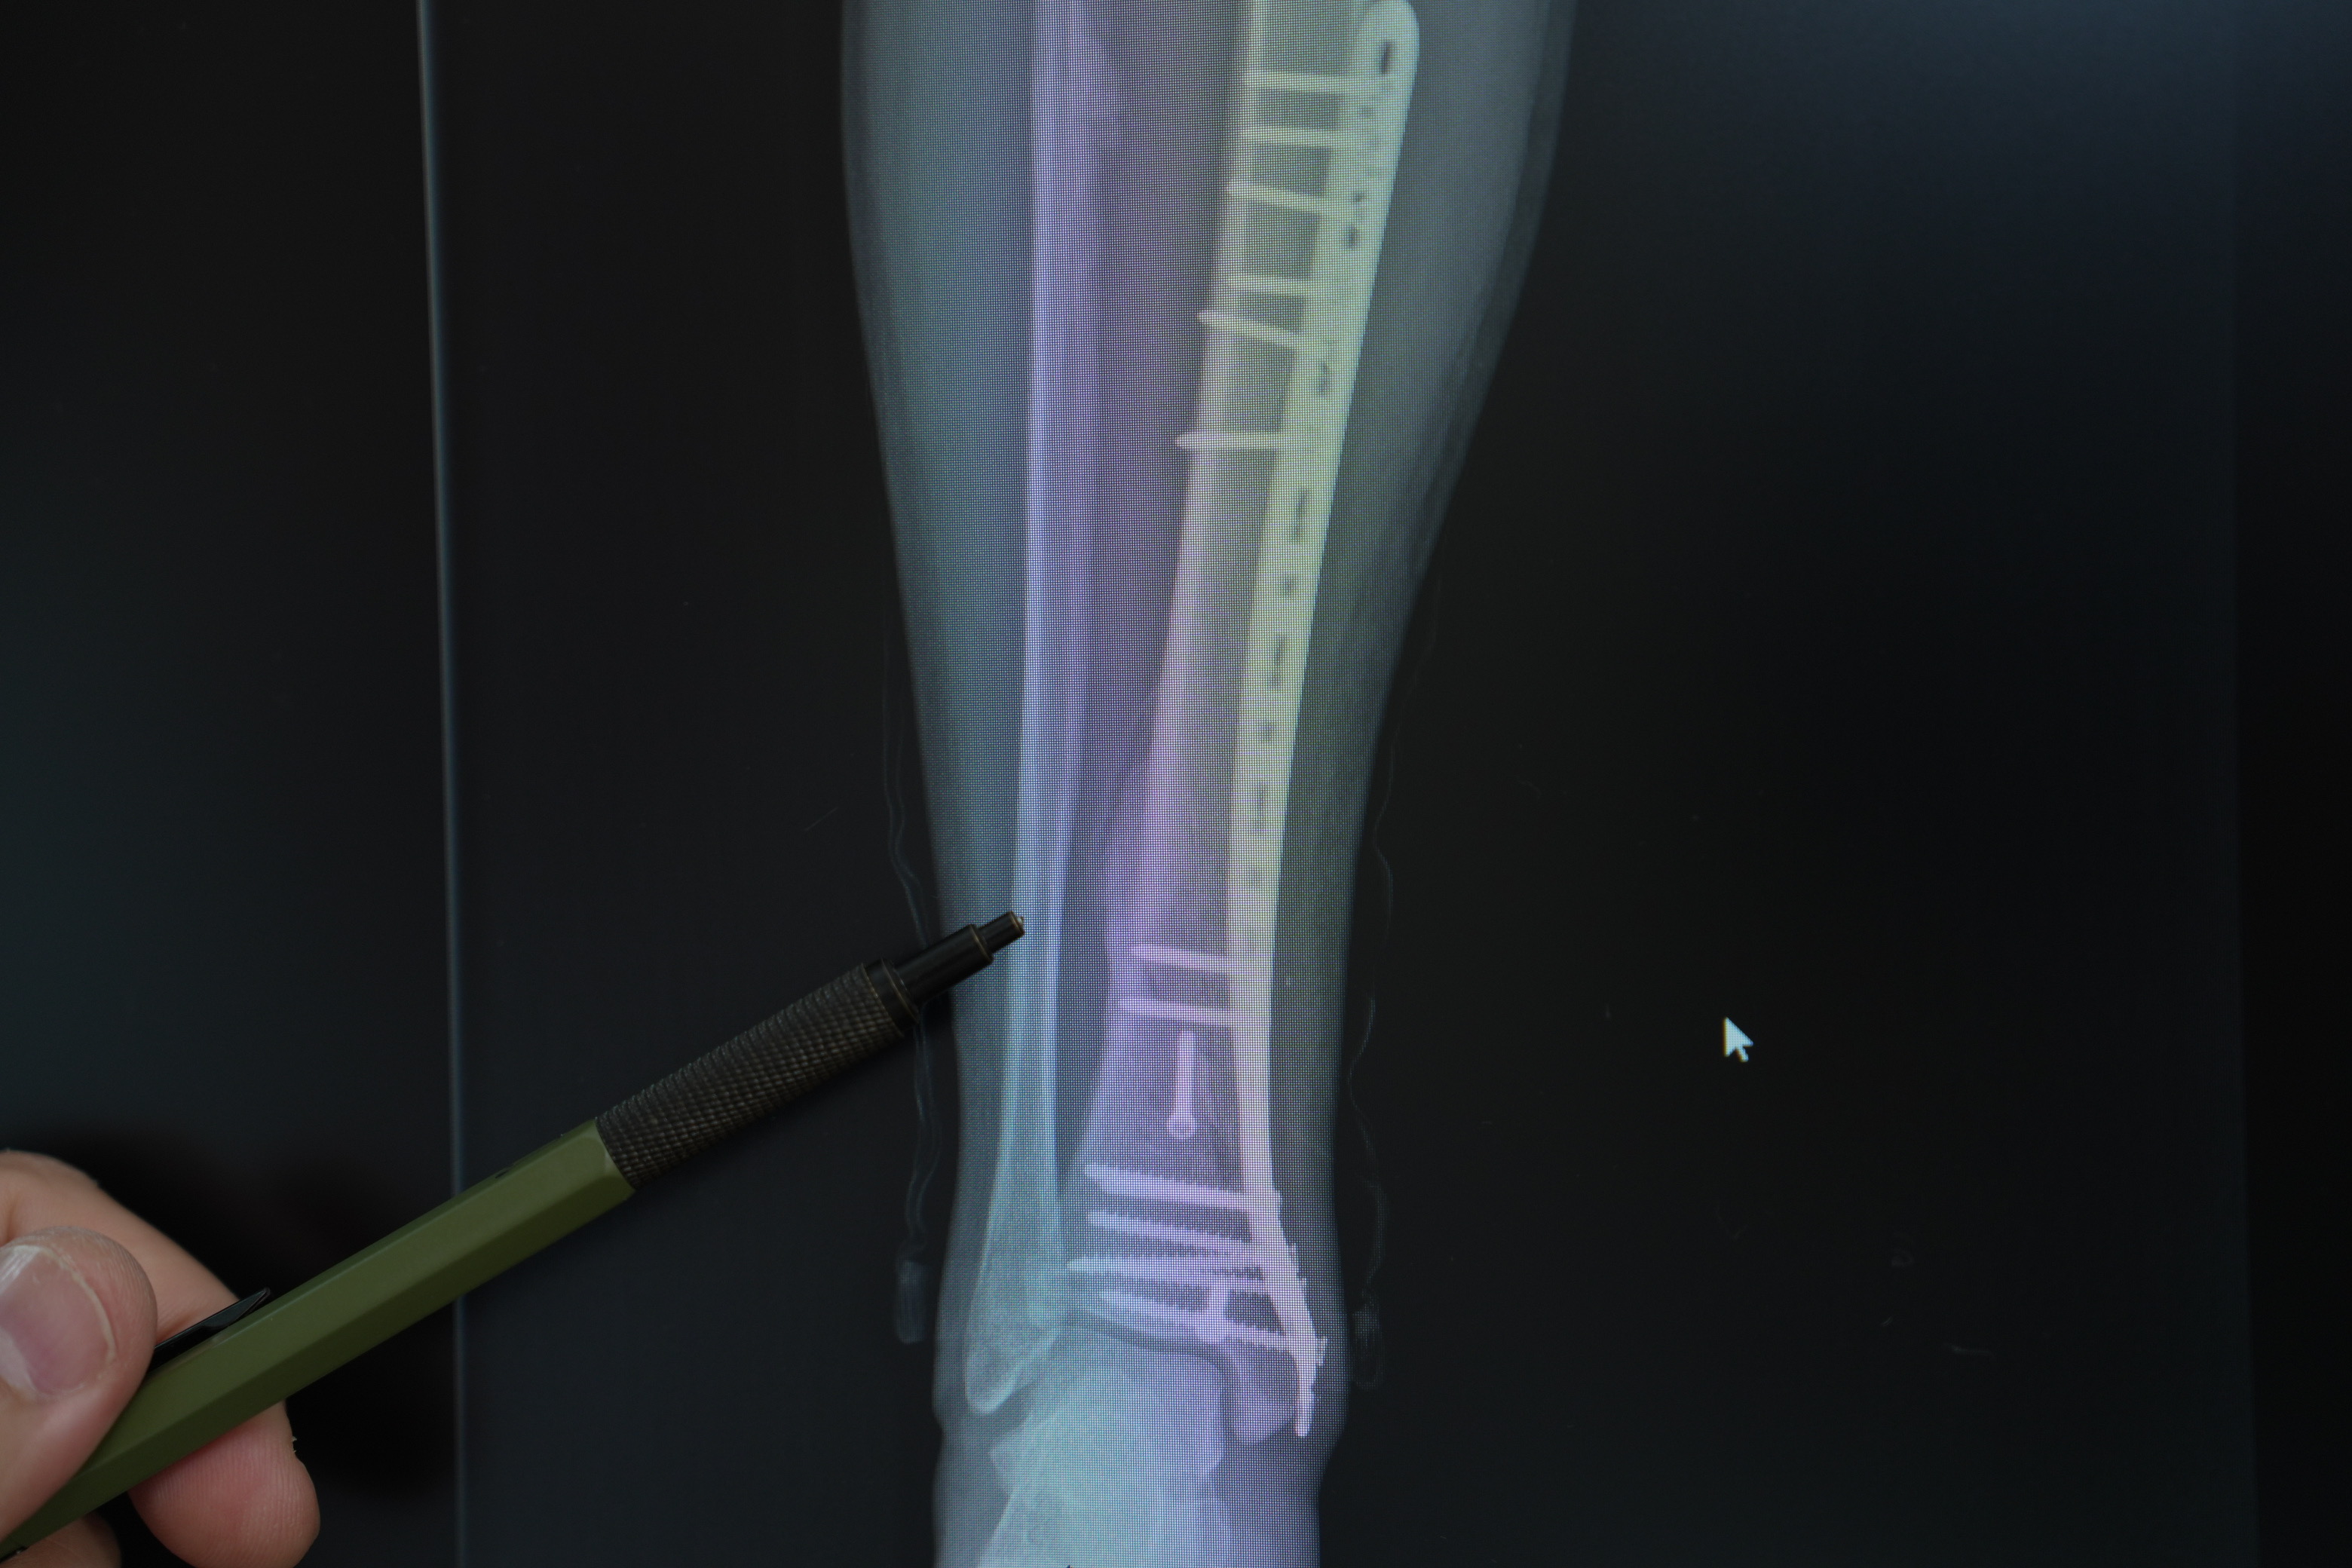

Trafikte motosikletlerin sayısı her geçen gün artıyor, ancak bu artış kazalar ve yaralanmalarda da belirgin bir yükselişi beraberinde getiriyor. Medipol Üniversitesi Pendik Hastanesi’nden Ortopedi ve Travmatoloji Uzmanı Dr. Öğr. Üyesi Mehmet Soyarslan, motosiklet kazalarının çoğunda kırık ve yumuşak doku hasarlarının görüldüğünü belirterek, “Eğitimsizlik, koruyucu ekipman eksikliği ve bilinçsiz kullanım, en büyük tehlike kaynağı. Acile başvuran motosiklet kazalarının yaklaşık yarısında kas iskelet sistemi hasarı, bu olguların da yüzde 30-40’ında kırıklar görülüyor” uyarısında bulundu.

Türkiye’de trafiğe kayıtlı 6,5 milyondan fazla motosiklet bulunduğunu vurgulan Dr. Soyarslan, “Bazı illerde, motosiklet sayısı artık otomobil sayısını geçmiş durumda. Pandemi döneminde hızla büyüyen kurye sektörü bu artışta büyük rol oynadı. Büyük şehirlerde ise trafik ve park sorunundan kaçmak için bireysel kullanım yaygınlaştı. Eskiden acillerde düşme ya da araç çarpışması nedeniyle yaralanmaları görürdük, şimdi motosiklet kazaları açık ara önde. Bu kazalar sadece kırıklarla değil, kafa, göğüs ve karın travmalarıyla da karşımıza çıkıyor” dedi.